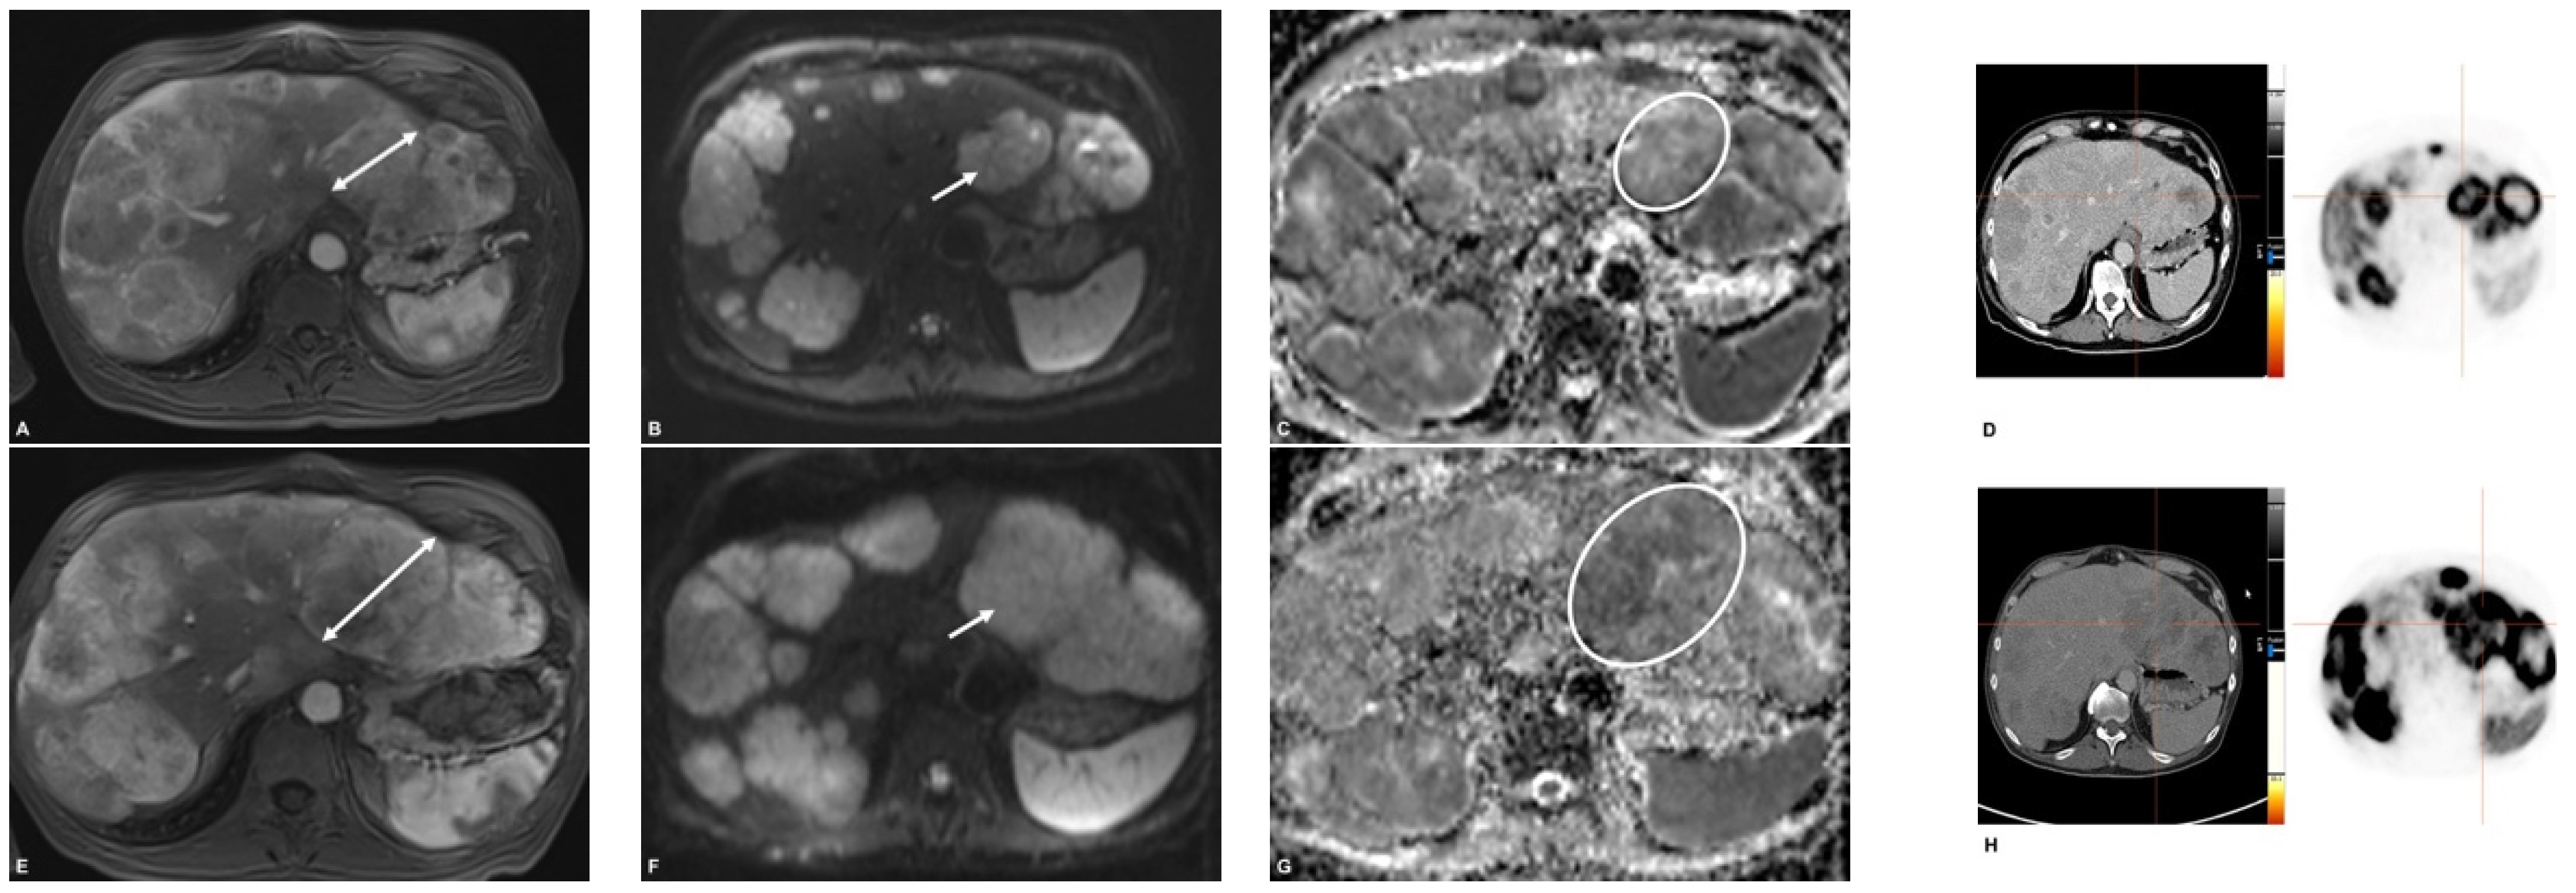

2.3. MR Imaging

2.4. PET/CT

2.5. Image Analysis

3.3. Response Assessment on First Follow-Up